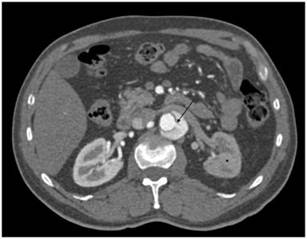

Figura 3 Caso de disección aórtica con sitio de reentrada y datos de hipoperfusión visceral. Paciente masculino de 64 años de edad con diagnóstico de disección aórtica; la flecha negra marca un sitio de reentrada a nivel de las renales, y el asterisco (*) muestra una disminución de la atenuación de la corteza renal izquierda al compararla con la contralateral.

Así mismo, los colgajos de disección pueden ser de diversa morfología, dentro de lo cual un dato importante a estudiar, sobre todo para la planeación del manejo terapéutico, es la cantidad de sitios de reentrada entre la luz falsa y la luz verdadera (fig. 3), ya que se ha visto que el número de reentradas puede asociarse a cambios en la movilidad del colgajo de disección, afectando el flujo intraluminal, que puede tener repercusiones hemodinámicas en el paciente11. En el presente estudio, el 50% de los casos no presentaron sitios de reentrada. El 18.8% tuvo un sitio de reentrada, mismo porcentaje obtenido en pacientes con 2 sitios de reentrada. No se observaron pacientes con 3 sitios de reentrada. Solo el 3.1% tuvo 4 sitios de reentrada, y el 9.4% de los pacientes tuvieron 5 o más sitios de reentrada. En el presente estudio no se encontró asociación significativa entre la mortalidad y los sitios de reentrada.